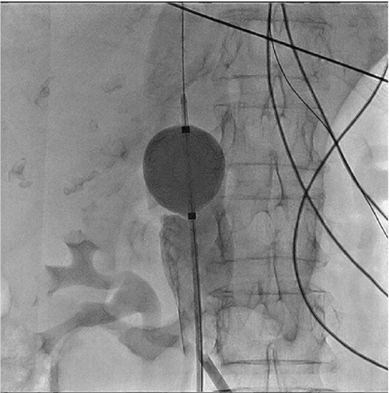

Figura 2 Proceso de inflado del balón hasta lograr la oclusión del defecto. A. Con el inflado parcial inicial se logra ubicar de manera precisa el sitio de la perforación. Este inflado parcial no ocluye el orificio y aún permite la salida de medio de contraste (flecha amarilla). B. Al inflar más el balón se logra la hemostasia (no se observa salida del medio de contraste). Cada uno de estos inflados se realizó por periodos de 5 a 10 minutos, con un periodo de un minuto entre inflado.

Mujer de 69 años, con antecedente de hipertensión arterial y fibrilación auricular paroxística, llevada a aislamiento eléctrico de venas pulmonares bajo anestesia general, en quien se realizó abordaje femoral bilateral, con dos introductores 5 F en el lado derecho (los cuales serían intercambiados posteriormente por introductores transeptales) y en el lado izquierdo con un introductor 11 F de 30 cm (Fastcath(, St Jude Medical, Saint Paul, Minnesota, Estados Unidos). Una vez realizadas las punciones, se procedió a infundir 5.000 unidades de heparina no fraccionada intravenosa. A través del introductor 11 F femoral izquierdo se avanzó una sonda de ecocardiografía intracardiaca (ecocardiografía intracardiaca) Viewflex Xtra( (St Jude Medical, Saint Paul, Minnesota, Estados Unidos) bajo visualización fluoroscópica, protruyendo por fuera del introductor 11F sin encontrar resistencia significativa durante el avance. No obstante, no fue posible avanzar más allá de la silueta hepática a pesar de maniobrar la sonda, motivo por el cual se decidió realizar una venografía a través del mismo introductor 11F. Se evidenció de esta manera una perforación de la vena cava inferior, con salida de la sonda de ecocardiografía intracardiaca hacia el espacio retroperitoneal (fig. 1). Una vez documentado esto, se revirtió el efecto de la heparina con protamina, se retiró la sonda de ecocardiografía intracardiaca y se ubicó el sitio exacto de la perforación, observándose salida del medio de contraste hacia el espacio retroperitoneal. Se decidió, entonces, avanzar una guía de alto soporte Amplatz Super Stiff( (Boston Scientific, Marlborough, Massachussets, Estados Unidos) 0.035'' a través de uno de los introductores femorales derechos, el cual se intercambió por un introductor 10F, para posteriormente avanzar un balón de alta distensibilidad (Reliant(, Medtronic, Minneapolis, Minnesota, Estados Unidos) hasta el sitio de la perforación. Una vez ubicado, se infló de manera progresiva hasta lograr la oclusión del defecto de la pared (fig. 2). Se realizaron varios inflados de 5-10 minutos cada uno, con 1 minuto de espera entre cada inflado. Con los inflados se logró una disminución progresiva de la cantidad de medio de contraste que fluía por la perforación, hasta lograr hemostasia sin necesidad de intervención quirúrgica (fig. 3). Al día siguiente de la intervención se realizó una angiotomografía de abdomen, en la cual no se observaron alteraciones anatómicas que explicaran la perforación. La paciente fue dada de alta 3 días después con terapia anticoagulante (apixabán 5 mg vía oral cada 12 horas) y continúa en buenas condiciones luego de dos años.